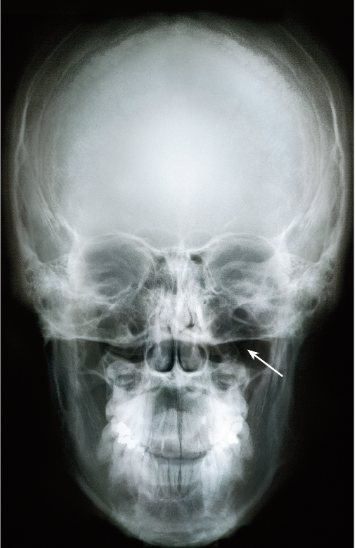

frontal sinus

sphenoidal sinus

ethmoid sinus

maxillary sinus